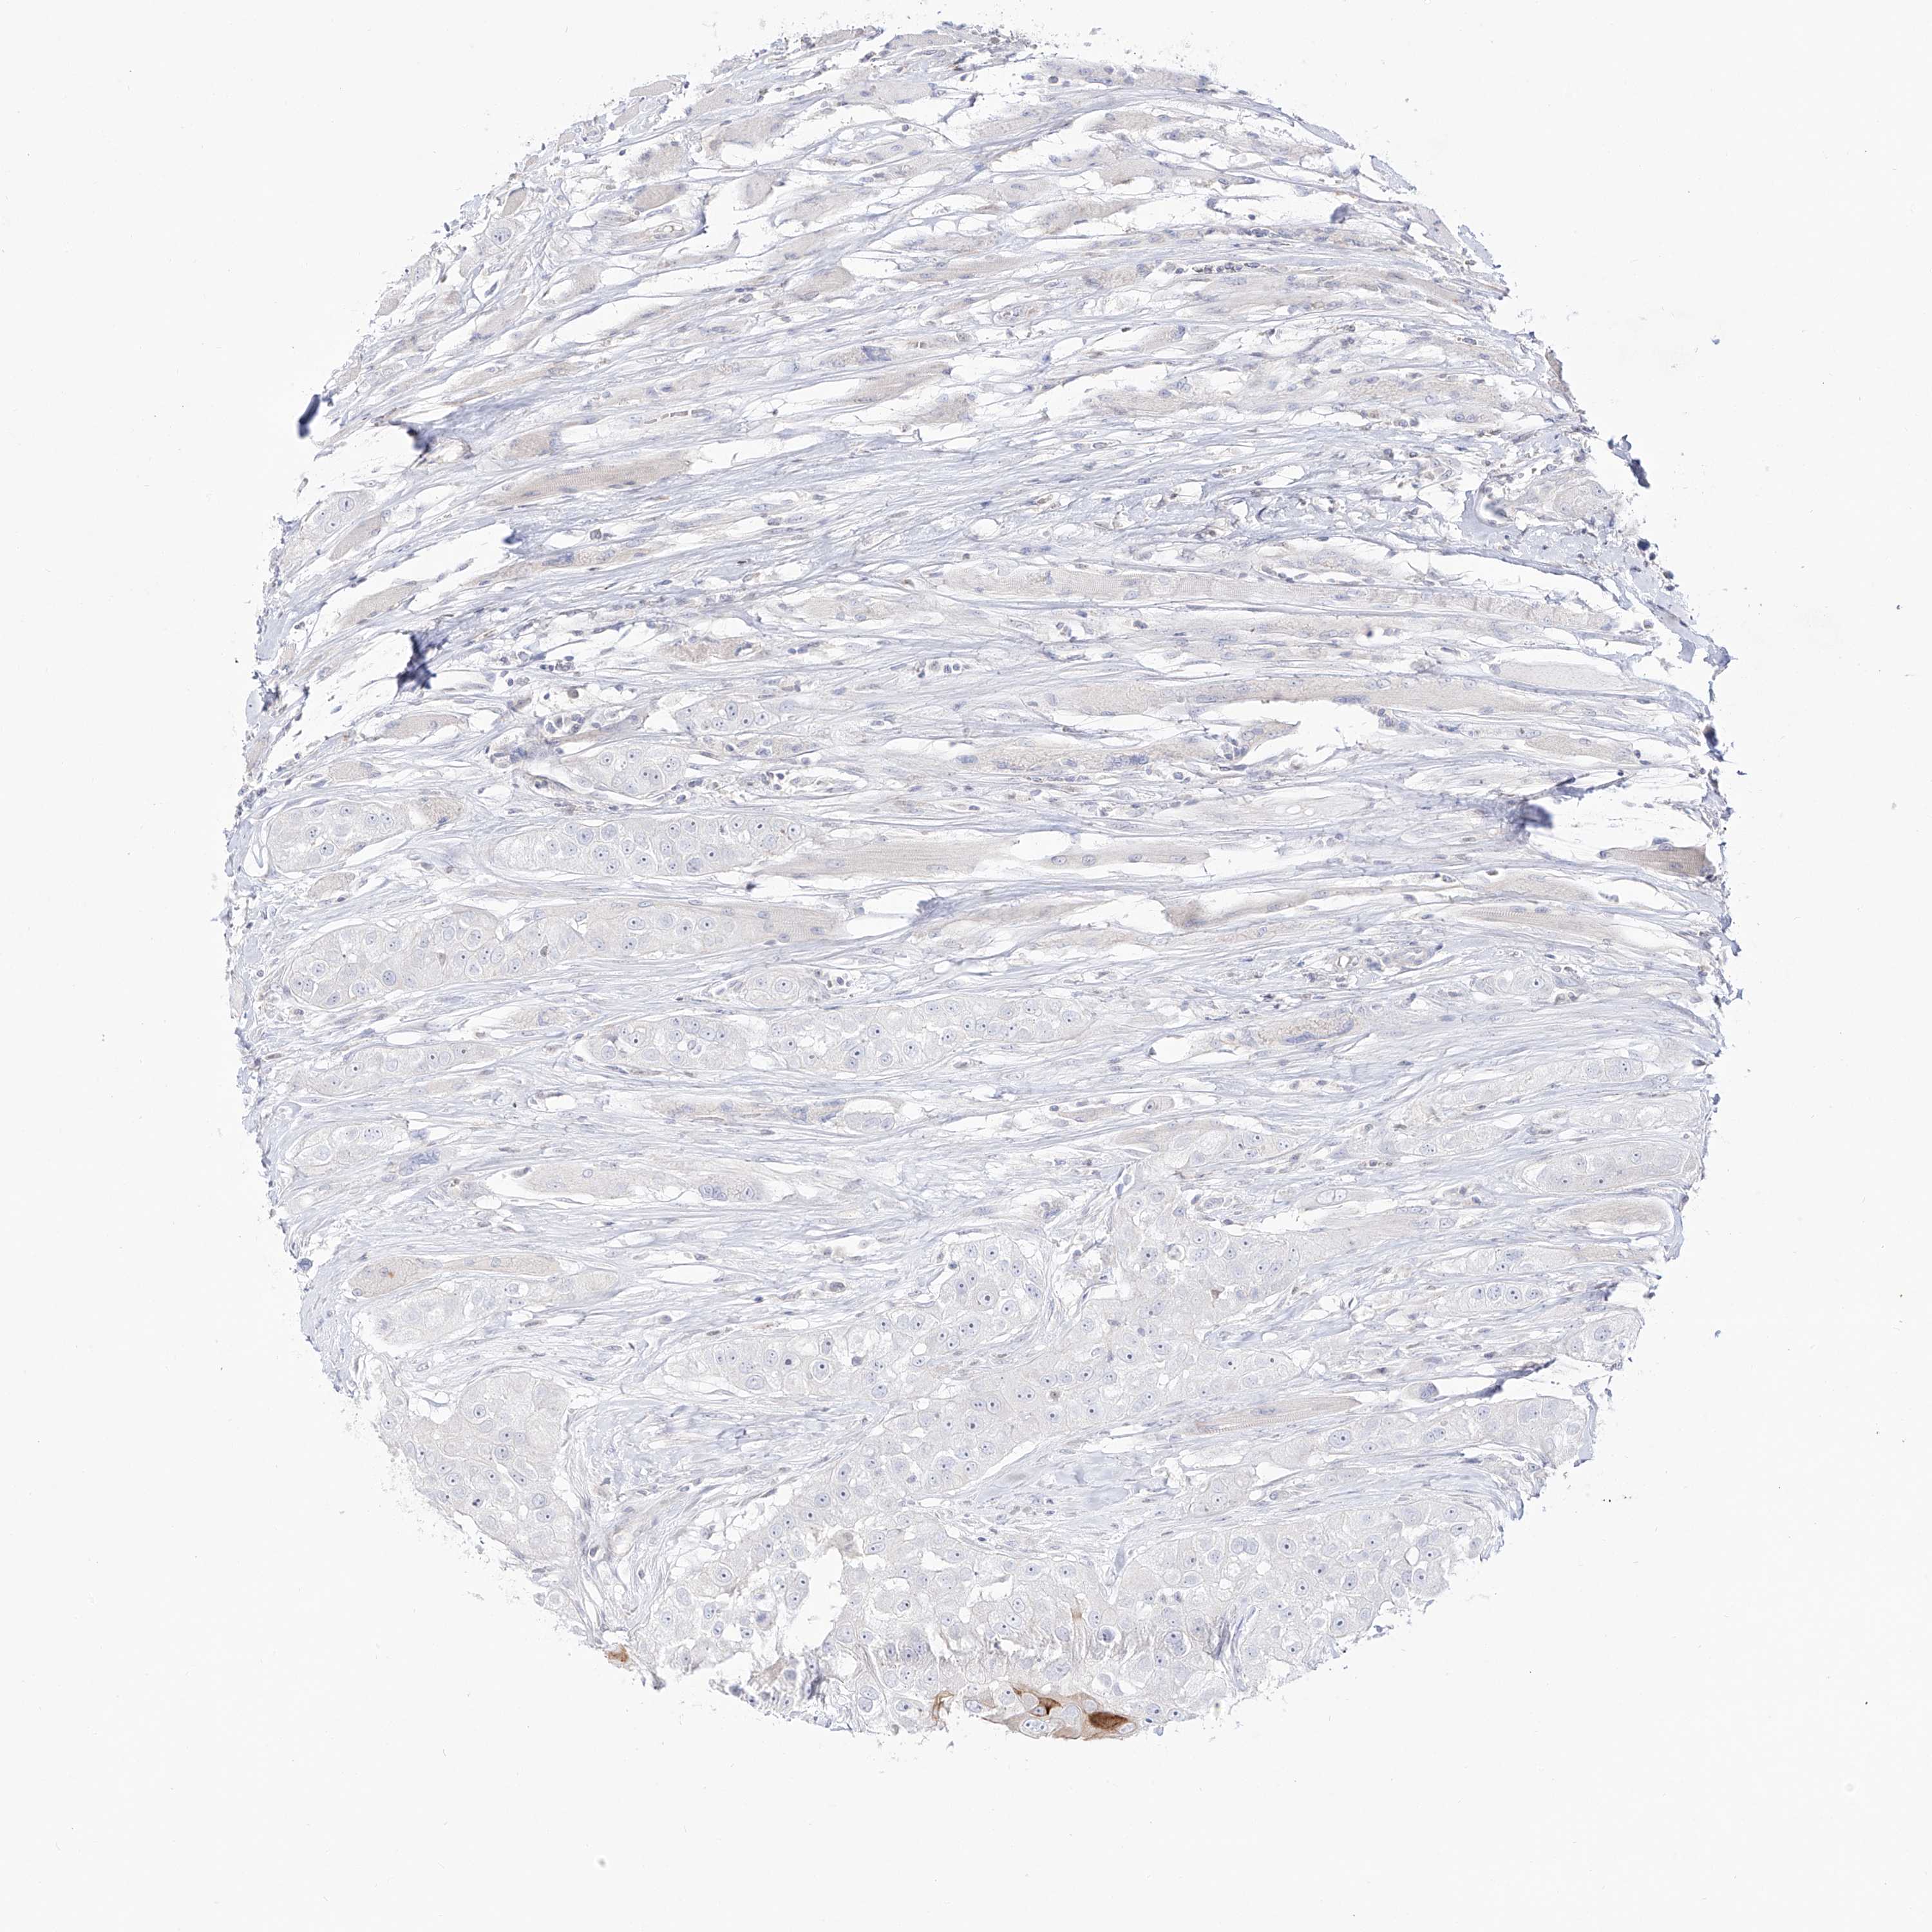

HEAD AND NECK CANCER - Protein expressioni

A mouse-over function shows sample information and annotation data. Click on an image to view it in a full screen mode. Samples can be filtered based on level of antibody staining by selecting one or several of the following categories: high, medium, low and not detected. The assay and annotation is described here.

Antibody stainingi

Antibody staining in the annotated cell types in the current human tissue is reported as not detected, low, medium, or high, based on conventional immunohistochemistry profiling in selected tissues. This score is based on the combination of the staining intensity and fraction of stained cells.

Each image is clickable and will lead to virtual microscopy that enables deeper exploration of all samples and also displays staining intensity scores, fraction scores and subcellular localization as well as patient and tissue information for each sample.

Antibody HPA029406

Antibody HPA071641

Squamous cell carcinoma, NOS

Squamous cell carcinoma, metastatic, NOS

Adenocarcinoma, NOS

Adenoma, NOS